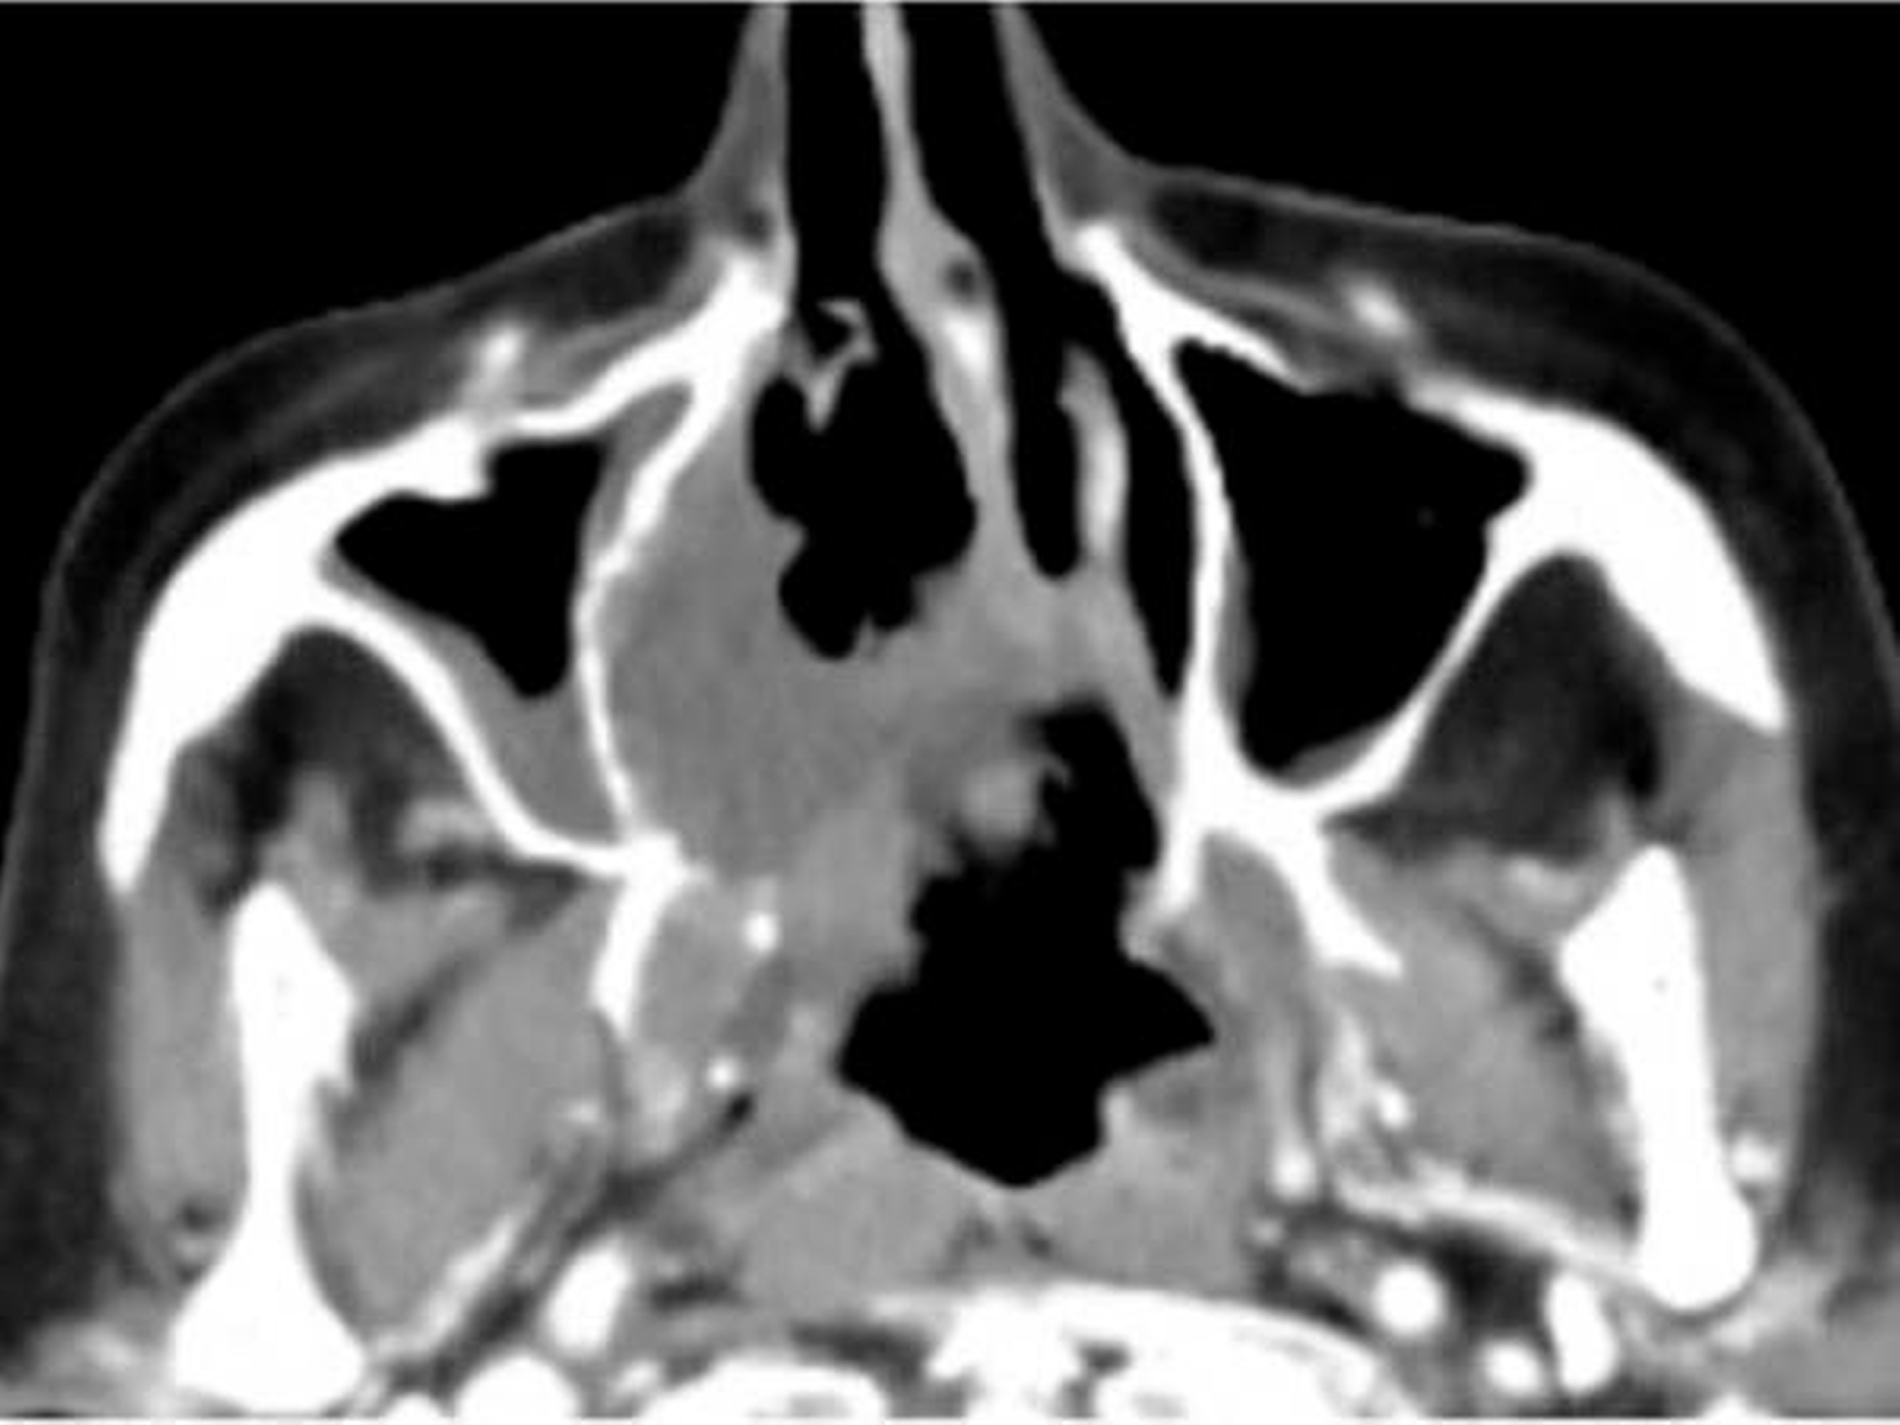

Die computertomografische Bildgebung zeigte eine inhomogene, kontrastmittelanreichernde und mittellinienüberschreitende Raumforderung im Bereich des Gaumens, die kaudal in die Mundhöhle und kranial in das Cavum nasi reichte. Die Größenausdehnung betrug circa axial 67 x 56 x kraniokaudal 52 mm.

Der Tumor wies multiple hypodense Anteile und einzelne Kalzifikationen auf. Die rechte Maxilla war distal der Regio 24 destruiert. Auch das Palatum durum et molle zeigten beidseits (rechtsbetont) Osteolysen bei primär verdrängendem Charakter auf. Der Nasopharynx war subtotal verlegt, die Uvula, der rechte M. constrictor pharyngis superior und beide Choanen nicht mehr abgrenzbar.

Der Tumor ragte durch die mediale Begrenzung des rechten Sinus maxillaris in die Nasenhaupthöhle mit einer hauchdünnen knöchernen Begrenzung. Rechts reichte die Raumforderung bis in die Fossa pterygoidea. Die Processus pterygoidei waren zentral aufgelöst. Rechtsseitig war die Anzahl der Lymphknoten in Level Ib und IIa/b vermehrt und moderat vergrößert, aber ohne klare Malignitätskriterien.